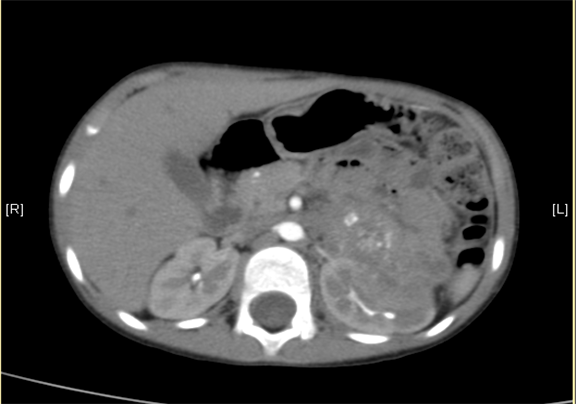

下腹部增强CT示:神经母细胞瘤。

术前CT检查:

平衡期